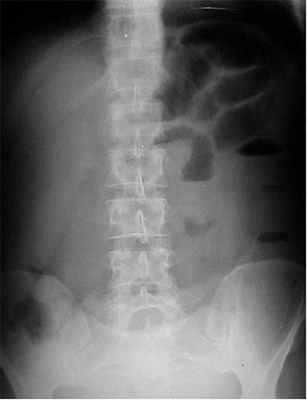

УЗИ брюшной аорты

Своевременная диагностика является залогом успеха в лечении абдоминальной ишемии, но она очень сложна. Учитывая, что возможность спасти жизнь при этой патологии имеется только в первые часы заболевания диагностика должна быть срочной и точной. Мезентриальный тромбоз можно спутать с любым острым заболеванием брюшной полости. Диагноз ставится методом исключения. В первую очередь необходимо исключить прободную язву, острый панкреатит, кишечную непроходимость. Наличие у пациента мерцательной аритмии, инфарктов в анамнезе, атеросклероза нижних конечностей позволяют предположить мезентериальный тромбоз. После исключения острых заболеваний брюшной полости проводятся специфические исследования для диагностики непроходимости сосудов брыжейки.

УЗИ брюшной аорты позволяет выявить тромбоз брыжеечной артерии или чревного ствола. Преимуществом метода является его быстрая доступность и отсутствие осложнений. Брюшная аорта осматривается в продольном и в поперечном срезе в режиме цветового картирования. Определяется скорость кровотока по аорте и ее ветвям. Метод обладает достаточно высокой чувствительностью, но его результаты зависят от опыта врача, проводящего исследование и правильной интерпретации полученных данных.